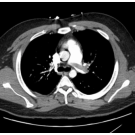

A 57-year-old woman with a history of hypothyroidism and breast cancer, for which she had undergone a mastectomy 10 years prior, presented to the emergency department with a 1-day history of right...

11/30/2022